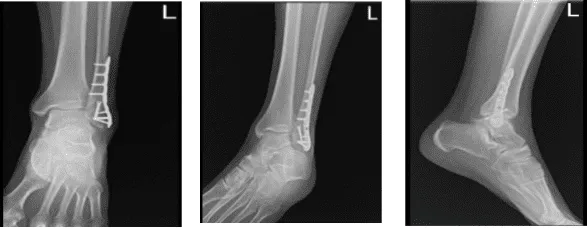

After a week from the surgery, the patient was sent for an X-ray. The AP, lateral and oblique. No prior examinations are available for comparison. Examination is performed through an overlying cast partially obscuring bony detail. The patient is status post ORIF distal fibular fracture.

The fracture line is barely visible. The surgical hardware is intact. Visualized aspects of the left talus, calcaneus and tarsal bones demonstrate intact cortical margins with no evidence of an acute fracture. There are no significant degenerative changes. Ankle mortise is well maintained.

There is no appreciable soft tissue swelling. There is no calcaneal plantar spur. It gives the impression that no prior examinations are available for comparison.

Examination is performed through an overlying cast partially obscuring bony detail. The patient is status post ORIF distal fibular fracture. The fracture line is barely visible. The surgical hardware is intact.

After weeks the patient went back to the office for his follow up checkup, with an x-ray of his ankle for review. He denies fever, chills, pain and he is WBAT with boots, no crutches. X-rays were reviewed and discussed, there is a surgically treated fracture distal left fibula.

A faint fracture line is visualized, the visualized distal left tibia is unremarkable and visualized aspects of the left talus, calcaneus and tarsal bones demonstrate intact cortical margins with no evidence of an acute fracture.

Ankle mortise is well maintained however, there is mild soft tissue swelling laterally and no calcaneal plantar spur.